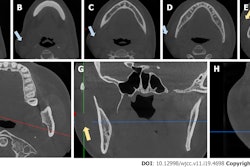

About 21 hours after her death, computed tomography images were taken, revealing subcutaneous emphysema from the right mandible to the cervical area. Also, gas was visible in the right mandibular canal, the right submental vein extending to the right anterior jugular vein, in the brain, cervical vessels, and chambers of the heart. It was estimated that about 100 mL of gas within the heart chambers, the authors wrote.

An autopsy revealed gas within the woman’s cerebral and anterior jugular veins and emphysema in the cervical soft tissues. A 0.5-cm patent foramen ovale was discovered in her atrial septum, they wrote.